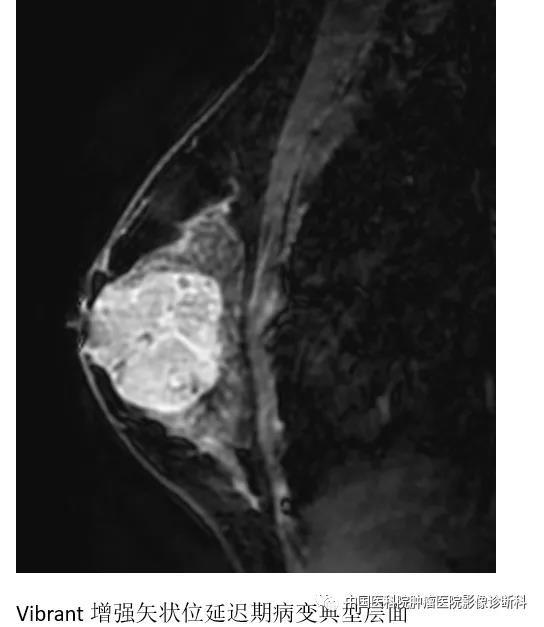

乳腺MR检查